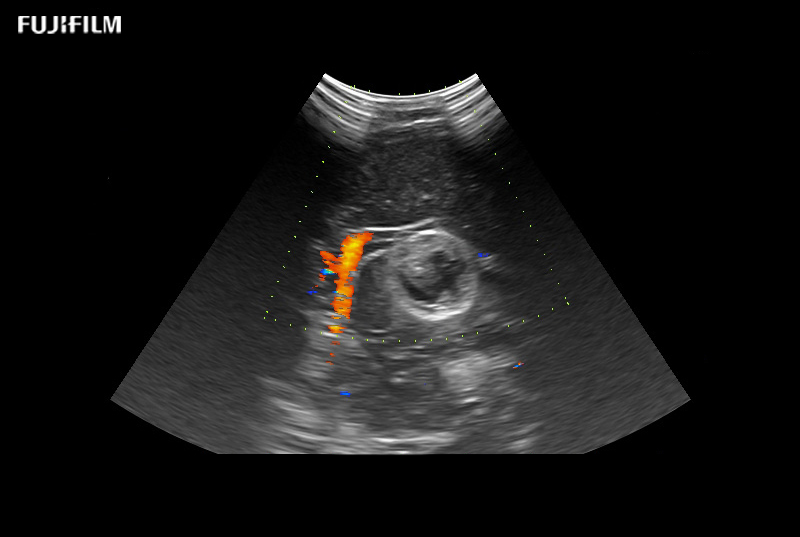

Liver Surgery Procedure using L46K1

Wide-view side-fire “T” transducer for open surgical procedures, providing exceptional near and far-field resolution, as well as trapezoid imaging to further expand visibility.